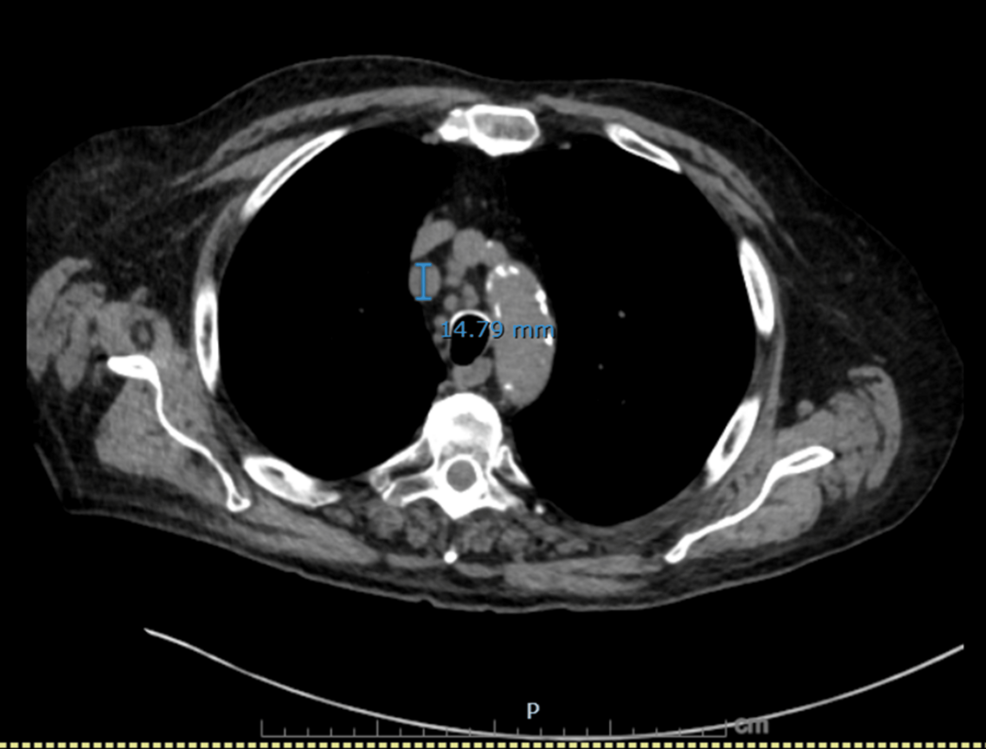

Figure 1: Axial CT chest showing an enlarged right paratracheal lymph node.

Axial image demonstrates a right paratracheal lymph node measuring 14.8 mm in short axis, concerning for malignant nodal involvement.